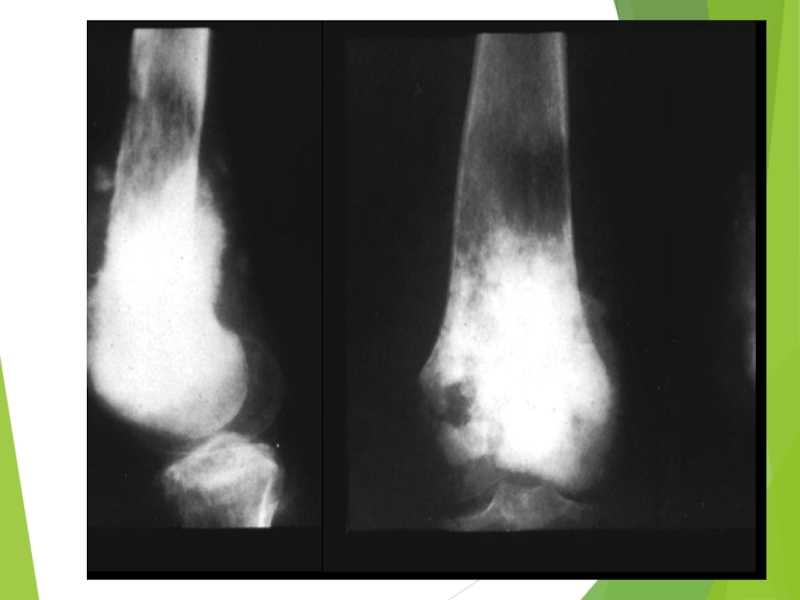

Слайд 54Ewing Sarcoma

The second most common bone tumor

The peak incidence is

appeared to be earlier than OS

The most common location: diaphyses of long bones, frequently bones of pelvis

The most common sites of mets: lungs and bones (20% of all pts have lung mets at the time of initial diagnosis), may be in bone marrow

Слайд 56“Onion skin” sign («луковая шелуха»)